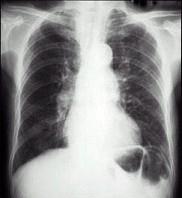

问题 老年男性,咳嗽、咳痰20余年,活动后气促10年。体检:桶状胸,两肺可闻及干、湿啰音,P亢进。心电图VV呈QS波,RV+SV=1.5 mV。胸片见图,因诊断为 ( )

选项 A.慢性阻塞性肺疾病急性发作 B.慢性阻塞性肺疾病 C.慢性阻塞性肺疾病、高血压性心脏病 D.慢性阻塞性肺疾病、慢性肺源性心脏病 E.慢性阻塞性肺疾病、心肌梗死

答案 D